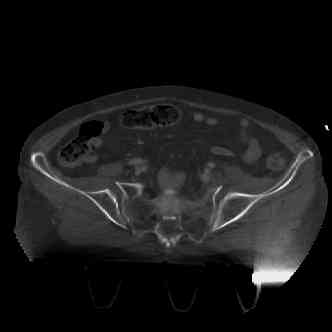

attached are images of a 70 year old female after peds versus car. her own car ran her over.

injuries are limited to the pelvis. left rami open and visible in a 10cm vertical laceration just lateral to left labia majora. wound is grossly clean. no vaginal and no urinary issues. CT scan shows widening of both SI joints anteriorly but I think this is vertically stable pattern.

pt treated that night with I/D and supra-acetabular frame to close the ring. consideration was given for SI screws bilateraly, but given time of night and other factors decision made not to proceed.

attached are several CT cuts. please let me know if you need more. the CT is pre-pelvic ex-fix placement.